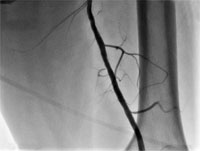

Рис.1. Дооперационная ангиография. Стеноз левой общей бедренной артерии до 90%.